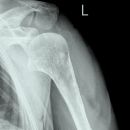

Schulter a.-p. (medizinisch)

Technik

• FDA: 1,15 m

• Ausgangsformat: 18/24 hoch

• Röhrenkippung: 15° cranio-caudal

• mit Raster

Indikation

entzündliche und degenerative Veränderungen (Arthritis)

Lagerung

sitzend/ stehend am Rasterwandstativ

nicht aufzunehmende Seite um 45° anheben

Hand in Neutralstellung (Ellenbogen Supination)

Zentralstrahl

Zentralstrahl: kurz unter Proc. coracoideus

Einblendung

oberes Licht 2 QF über Schulter-Haut-Grenze

laterales Licht Hautgrenze

Bemerkung

Bei Fragen im Subacromial-Raum sollte dieser überlagerungsfrei dargestellt werden.